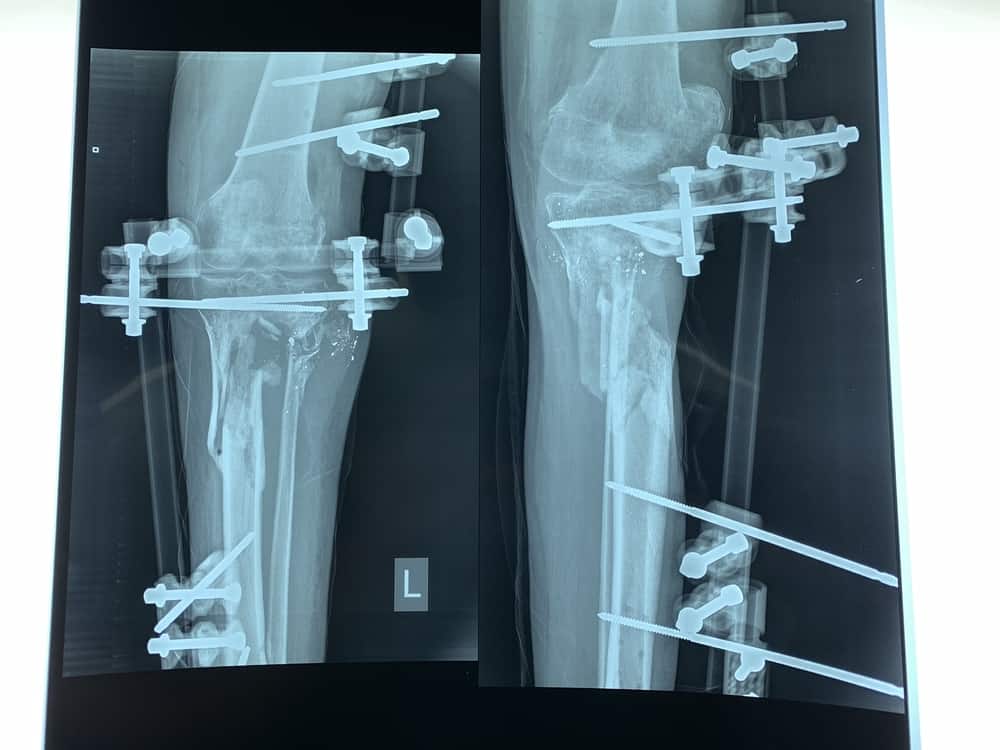

Unfortunately, as ghastly as the gap left by the bullet in Yousri’s bone was, his case was relatively simple. In protests held along the fence that separates Gaza from Israel since March 30th, 6,174 people have been injured by live bullets fired by the Israeli army. Nearly 90% of those were injured in the lower limbs. MSF has provided care for around half of the wounded after their initial treatment in local hospitals, and the wounds we have observed have been unusually severe. Patients have complex open fractures – where the bone is exposed to the air – in half the cases and severe tissue and nerve damage in most of the rest. Many patients are missing huge parts of their leg bones: if two centimetres leaves such a big hole, just imagine ten.

When the gap is bigger, like the six centimetres missing in the shin of Salim*, then it is not possible to do a bone graft straight away. Dr Mohammed Obaid, an MSF surgeon from Gaza, explained that this was a complicated case. “There was a raw area: the patient had an open wound, no skin, so the plastic surgeon made a covering of muscle from another part of the leg four weeks ago. Now we will open the wound again, clean it, and put bone cement inside.” This cement is putty with a pungent smell close to that of petrol. At first malleable, the surgeons massage it into the bone gap and mould it into the required shape. The cement quickly hardens and, over six to eight weeks, prepares the area to receive a bone graft. “When we are sure that there is no infection in the bone, and that the flap we have covered the wound with is good then we can reopen the area, take the cement out, and put the bone in,” Dr Obaid said.

For the most serious patients, however, the treatment that they need is very difficult to obtain in Gaza, a crowded piece of land that has been blockaded for the past ten years, and isolated for a lot longer. Therefore MSF is also transferring patients from Gaza to its reconstructive surgery hospital in Amman, Jordan. This is a complicated process that requires permission to travel from many sets of different authorities: permission that is often denied. However, MSF was recently able to send its first patient injured in the protests – Eyad, 22 – out of the Palestinian enclave. He had been shot on May 14 – the bloodiest day of the protests – and requires a bone graft and reconstructive surgery to repair the damage to his leg. The health system in Gaza is currently only able to offer this type of surgery to very few patients.